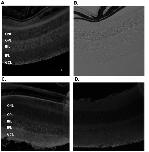

Figure 4. Binding of scFvs to native GABA receptors in mouse retinal sections.Immunohistochemistry of cryosections of mouse retina incubated with 600-α1 A10 scFv, (A and B), 300 nM biotinylated ZF130H1, negative control scFv (D) or 47 nM of anti-GABAA positive control antibody (C). Streptavidin (SA)-Cy5 or anti-rabbit IgG-Cy5 was used as the secondary detection reagent. Panels A, C and D are images obtained under fluorescent light (Cy5 filter), while panel B shows the image acquired under bright light. Representative images from three independent trials are shown. Scale bar depicts 80 µm. Legend: GCL; Ganglion cell layer, INL; Inner nuclear layer, IPL; inner plexiform layer, ONL; outer nuclear layer, OPL; outer plexiform layer.